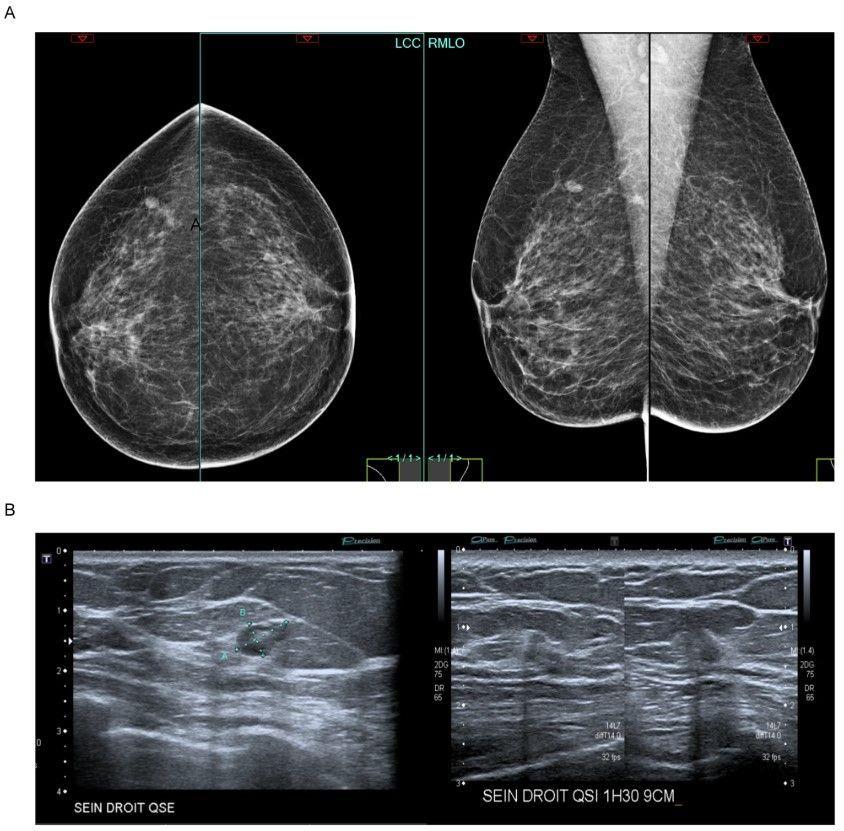

Misdiagnosis in breast imaging can delay treatment, cause unnecessary procedures, and erode patient trust, leading to worse prognosis and raise healthcare costs.

How do we address this? Accurate imaging, continuous education, and clear communication among providers are key to minimizing risks and improving patient care. (Isabelle Thomassin-Naggara et al.)